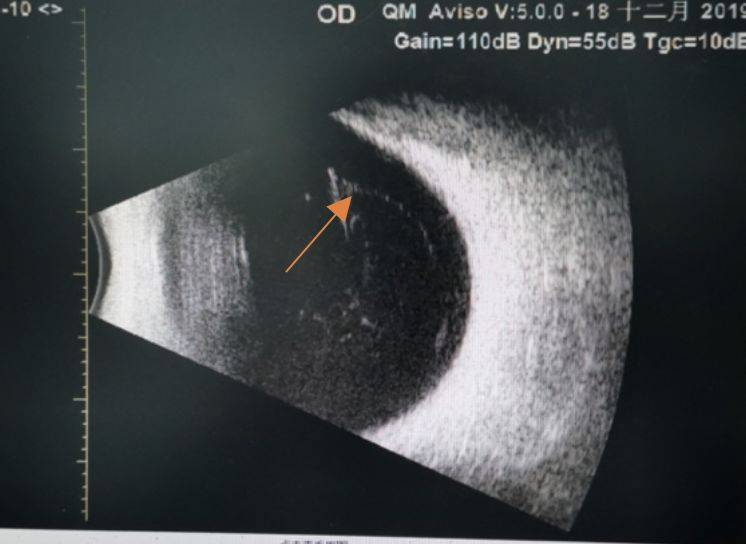

飞蚊症的症状,就是有个蚊子一直在眼前飞,这个蚊子不是真蚊子,现代医学认为:眼球里面玻璃体浑浊,导致眼睛看东西时有一团黑影,这就是飞蚊症。其实,中医把这个病叫“云雾移睛”,意思是那些云雾类浑浊的东西移到眼睛里了。不同的表达,差不多的意思。